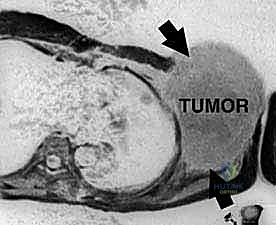

استئصال حزام الكتف: دليل شامل لجراحة الأورام الخبيثة والحفاظ على الطرف مع الأستاذ الدكتور محمد هطيف في صنعاء

تعرف على جراحة استئصال حزام الكتف المتقدمة لعلاج أورام الساركوما الخبيثة، وأهمية الحفاظ على الطرف. يقدم الأستاذ الدكتور محمد هطيف في صنعاء …